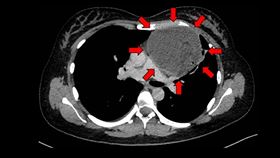

妹子胸口痛以為懷孕 胸腔長了巨大畸胎瘤

來自香港31歲的梁小姐,2年前開始偶爾會有胸口悶痛的...